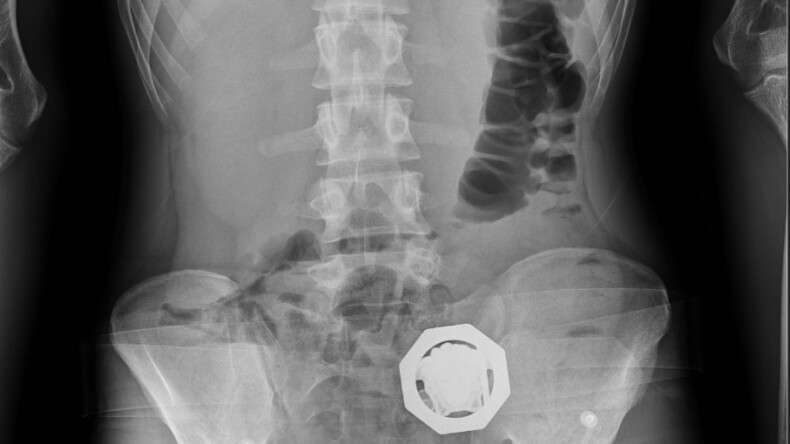

Diyarbakır’da, bir otomobildeki 4 şüphelinin midelerinde 121 parça halinde 840 gram eroin tespit edildi. Uyuşturucu çıkarılırken, 4 şüpheli tutuklandı.

İl Emniyet Müdürlüğü Narkotik Suçlarla Mücadele Şube Müdürlüğü ekiplerince yapılan çalışmalarda, doğu illerinden Diyarbakır’a geldiği tespit edilen otomobil, Bağcılar Mahallesi’nde durduruldu. İçinde bulunan 4 şüphelinin üst aramalarında herhangi bir suç unsuruna rastlanılmadı. Ancak şüpheliler, tedirgin haller sergilemeleri ve rahatsızlık belirtisi vermeleri üzerine, hastaneye götürüldü. 4 şüphelinin çekilen röntgenlerinde midelerinde 121 parça halinde 840 gram eroin tespit edildi. Uyuşturucular, yapılan tedavinin ardından çıkarıldı. Şüpheliler, işlemlerinin ardından sevk edildikleri adliyede çıkarıldıkları mahkemece ‘Uyuşturucu veya uyarıcı madde ticareti yapma veya sağlama’ suçlarından tutuklanarak cezaevine gönderildi.(HABER MERKEZİ)